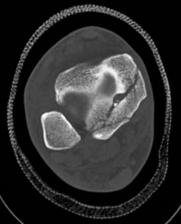

Standard orthogonal radiographs (anteroposterior and lateral) are sufficient for initial diagnosis, but they routinely underestimate the complexity of partial articular fractures. A high-resolution computed tomography (CT) scan with two-dimensional multiplanar reformats (coronal and sagittal) and three-dimensional surface rendering is considered the standard of care.

CT imaging is critical for:

1. Identifying the exact location and size of the articular fragments.

2. Detecting central articular depression that is obscured by the cortical rim on plain films.

3. Mapping fracture lines extending into the diaphysis.

4. Planning the surgical approach to ensure direct access to the primary fracture line.